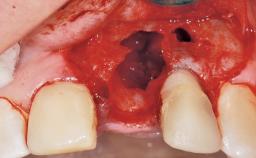

Immediate Flapless Placement of an Implant in a Maxillary Right Lateral Incisor Site

This 43-year-old male patient, a non-smoker, came to our practice because of a fracture of tooth 12 caused by a bicycle accident. Due to the combined para- and infrabony crown and root fracture, tooth extraction, and subsequent implant placement were suggested to the patient as the therapy of choice. The patient had high esthetic expectations with regard to the treatment outcome and asked for an immediate fixed provisional restoration. His individual esthetic risk profile summed up to a medium esthetic risk.